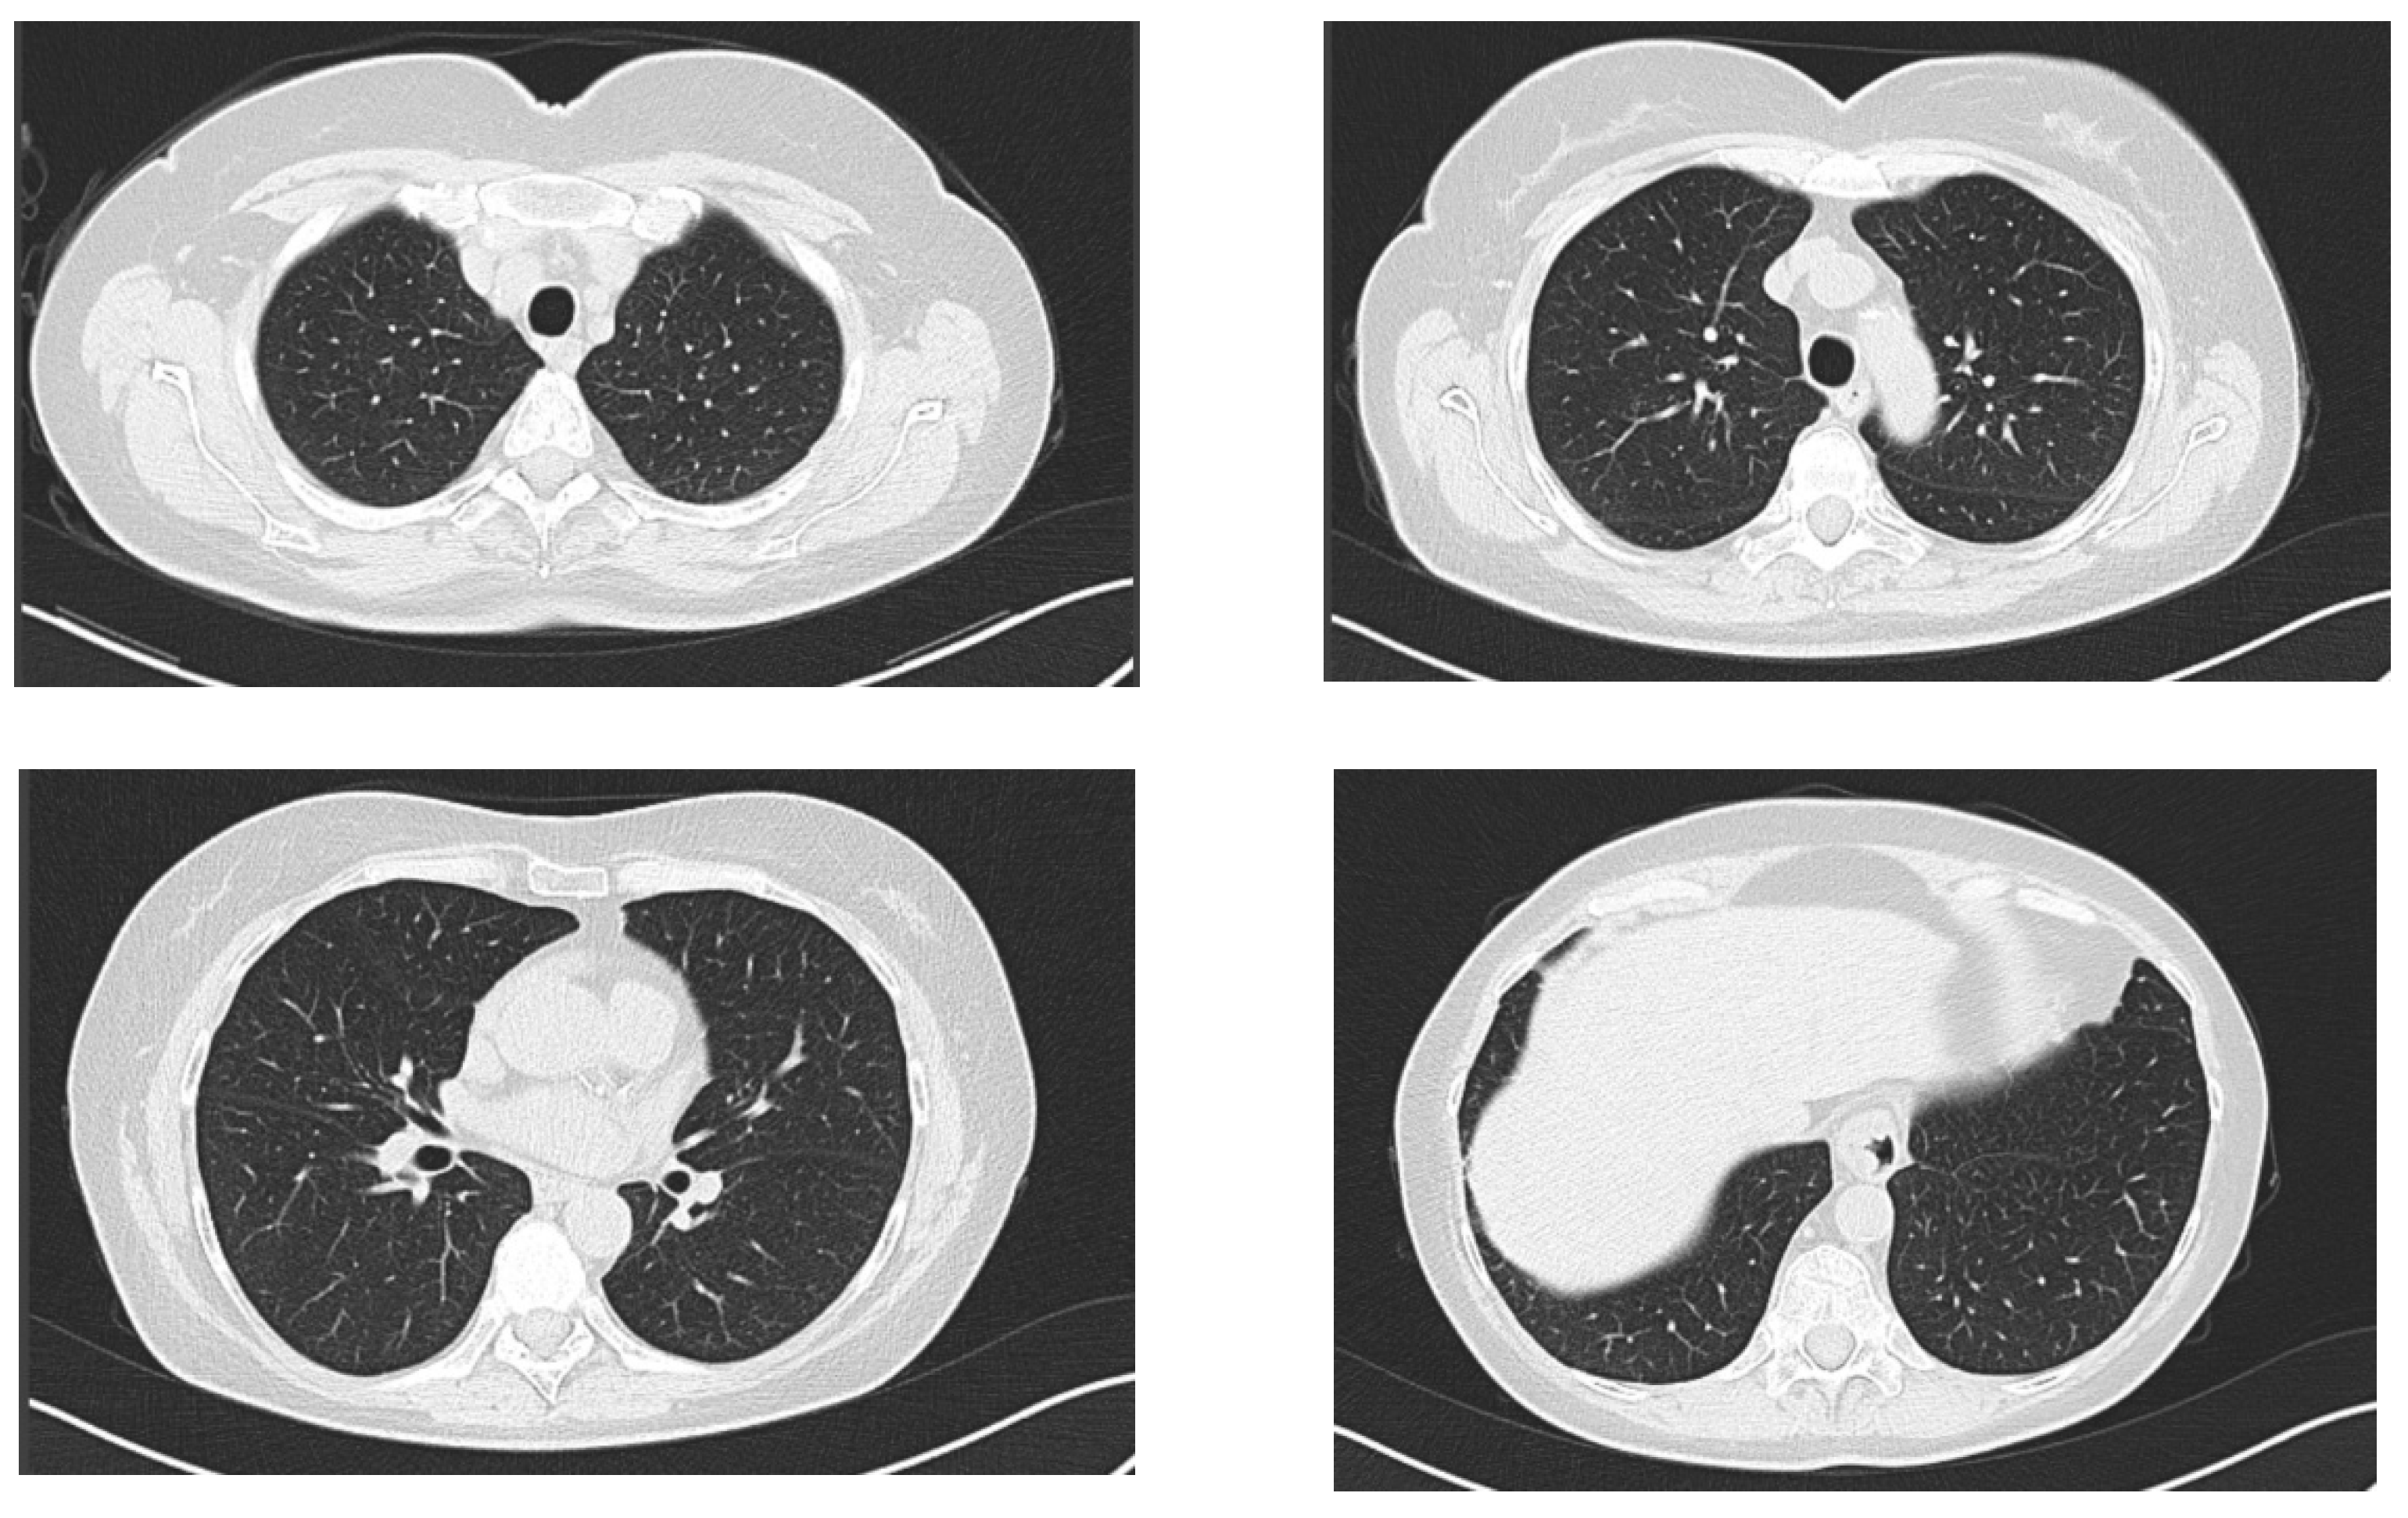

2.1. Case Report 1

2.2. Case Report 2